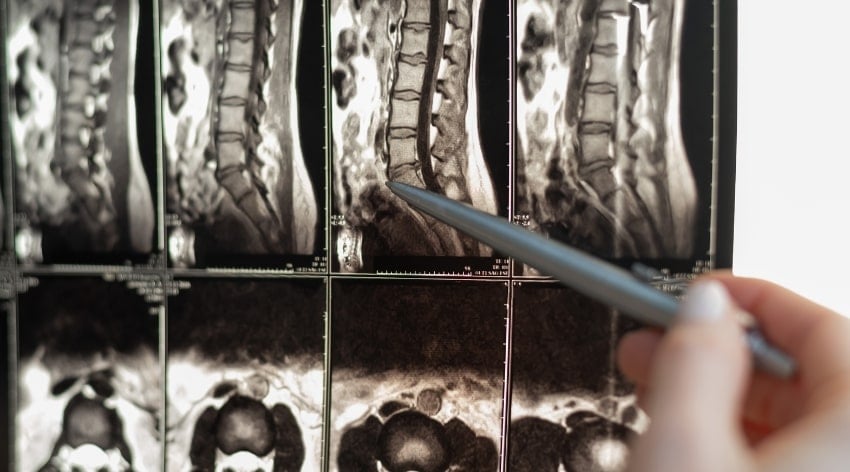

Scolioza lombară sau toracală este o curbură laterală a coloanei vertebrale care se poate dezvolta la adulți atunci când articulațiile fațetei și discurile încep să se deterioreze. Articulațiile fațetei conferă coloanei vertebrale flexibilitate, permițându-ne să ne răsucim, să ne întindem sau să ne curbăm pe canapea.

Când aceste articulații se deteriorează, oasele coloanei vertebrale se pot înclina și pot începe să se deplaseze într-o parte dezvoltându-se astfel scolioza.

Scolioza degenerativă se dezvoltă ca urmare a procesului natural de îmbătrânire și degradare a țesuturilor din coloana vertebrală. Odată cu trecerea timpului, discurile intervertebrale pot deveni mai subțiri și mai puțin elastice, iar articulațiile și vertebrele pot suferi uzură. Toate aceste modificări pot duce la o curbură laterală anormală a coloanei vertebrale – ceea ce numim scolioză degenerativă.